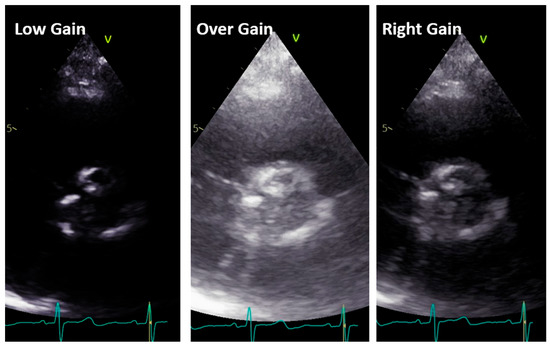

- Gain adjustment: The gain controls the amplification of the returning ultrasound signals. It is important to optimize the gain settings to achieve optimal image quality. Excessive gain can result in a bright image with noise, while insufficient gain can make the image too dark. Adjusting the gain appropriately ensures optimal visualization of cardiac structures (see later).